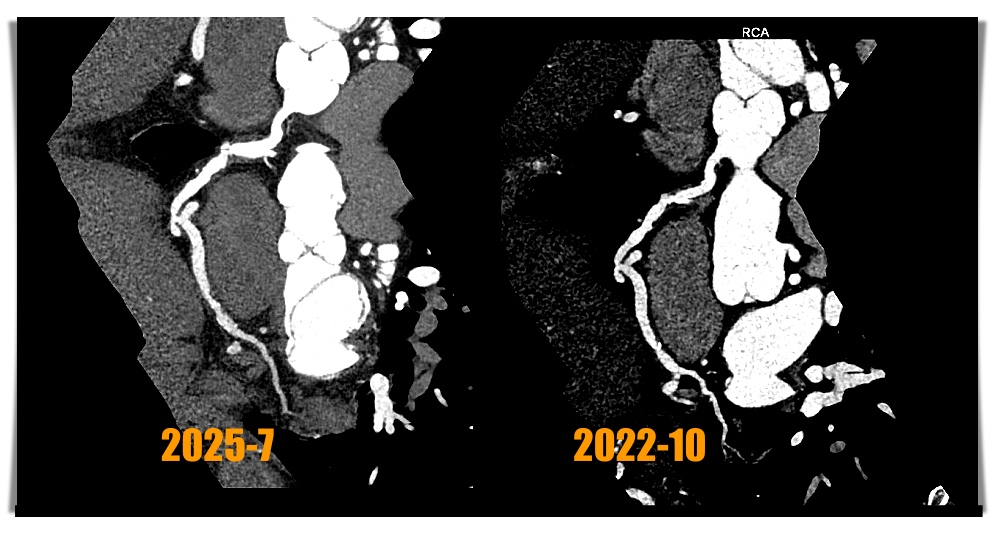

The third CCTA of the patient was performed on July 1, 2025 and showed calcium scores was 213 points (Fig 1) and coronary artery ectasia (CAE) of RCA and a 90% stenosis with high risk plaque with low-attenuation density and positive remodeling and spotty calcification at middle RCA (Fig 2 and 3) and a 80% stenosis with focal calcification and stable plaque at distal RCA. So regarding his RCA lesions of CCTA finding, the patient received coronary artery angiogram and coronary intervention.